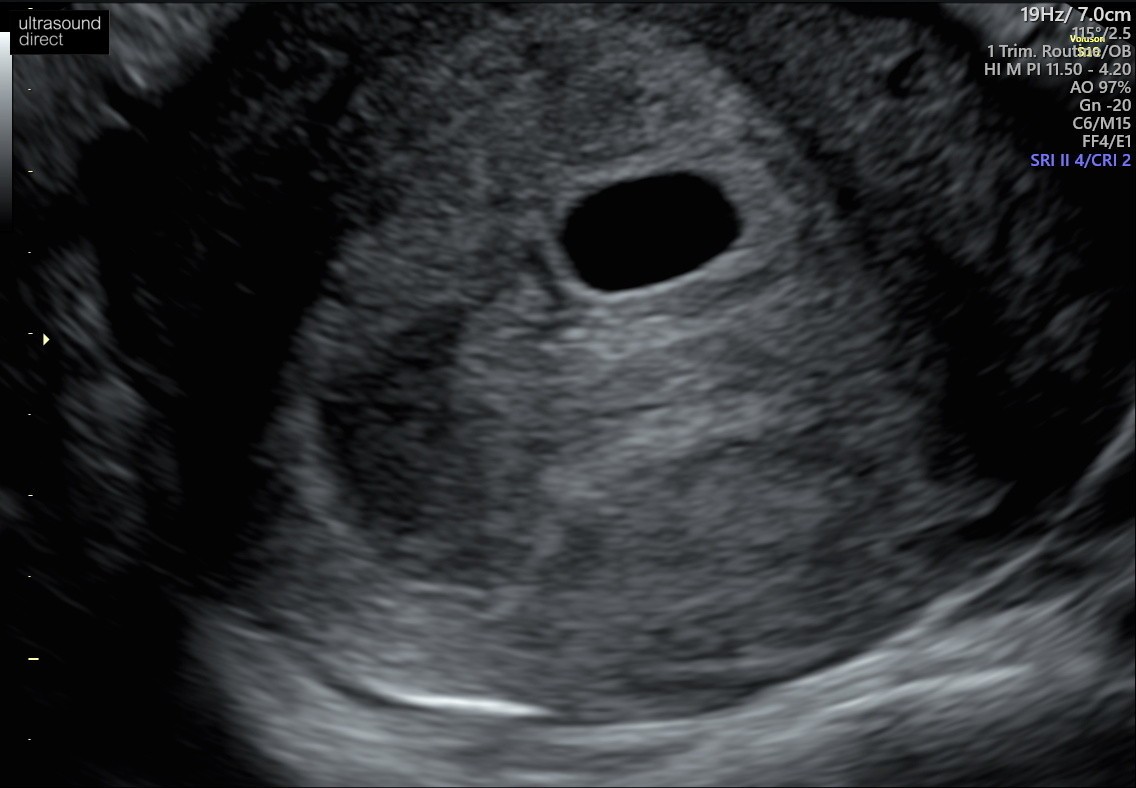

Ostatnia miesiączka 30 maj. Cykle ~32 dni. Z usg około 7 tydzień z kawałkiem. Byłam 22 lutego na usg - puste jajo płodowe. Pęcherzyk 1,78cm. Beta hcg ponad 50.000. Dostałam skierowanie do szpitala i tutaj moje pytanie - czy mam czekać? Jest szansa, że zarodek jeszcze się pojawi? Czy już nie robić sobie nadziei? Nie mam żadnych plamień ani krwawień, a czytałam dużo historii, że zarodek pojawił się w późniejszym czasie.

Moja historia raczej nie pocieszy, ale miałam podobną sytuację niemal 2 lata temu. Beta rosła książkowo, żadnych plamień, ale mój obraz USG wyglądał identycznie jak Twój. Diagnoza - puste jajo płodowe. Wymagało łyżeczkowania ze względu na wysoką betę. Moim zdaniem lekarz ma rację i myślę, że dla własnego dobra, po prostu lepiej nastawić się na potwierdzenie jego diagnozy. Przed zabiegiem i tak wykonują jeszcze jedno bardzo dokładne USG, więc nie ma szans, że przeoczą żywą ciążę. Mam nadzieję, że nie zabrzmiałam nieprzyjemnie. Na pocieszenie, po zielonym świetle od lekarza, po 4 miesiącach byłam już w ciąży i synu sobie właśnie smacznie obok śpi.

Niestety, ale też uważam, że lekarz ma rację. Przy becie 10000 powinno być widać serduszko. Twoja beta wynosi 50000.